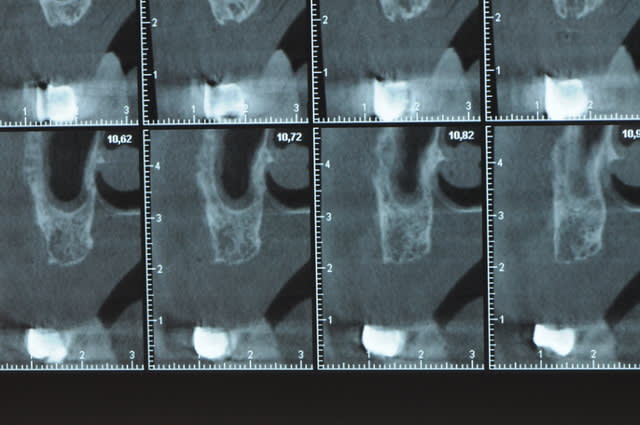

Une petite étude de ton cas D57

Sous réserves bien sur de voir l’animal en vrai

Les zones exploitables radiologiquement parlant:

Coupes implant

2,3 40100

4,96 35130 avec sinus lift mais difficile

5,25 35150

6,02 35130

6,78 35115 après réduction de hauteur de crête

7,26 35115 après réduction de hauteur de crête

8,51 35150

10,43 40115 ou 50115

11,10 40115

Ce qui nous fait 9 implants possible évidement avec un comblement de sinus on augmenterait encore les zones implantable mais ce n’est pas le but recherché, avec 8 (4+4) il doit être possible de faire une belle barre support de complet